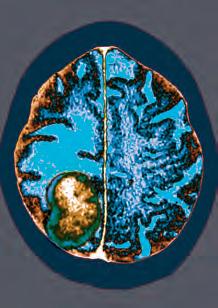

Researchers have created a new type of microelectrode array for brain–computer interface platforms.

The technology – CMU Array – holds the potential to transform how doctors are able to treat neurological disorders, the team claims.

The ultra-high-density microelectrode array (MEA) is 3D printed at the nanoscale and fully customisable. This means that one day, patients suffering from epilepsy or limb function loss due to stroke could have personalised medical treatment optimised for their individual needs.

The team, from Carnegie Mellon University in the US, applied the newest microfabrication technique, Aerosol Jet 3D printing, to produce arrays that solved the major design barriers of other brain computer interface (BCI) arrays.

Rahul Panat, one of the study authors, said: “Aerosol Jet 3D printing offered three major advantages – users are able to customise their MEAs to fit particular needs; the MEAs can work in three dimensions in the brain; and the density of the MEA is increased and therefore more robust.”

MEA-based BCIs connect neurons in the brain with external electronics to monitor or stimulate brain activity. They are often used in applications like neuroprosthetic devices, artificial limbs, and visual implants to transport information from the brain to extremities that have lost functionality. BCIs also have potential applications in treating neurological diseases, such as epilepsy, depression, and obsessivecompulsive disorder. However, existing devices have limitations.

bit.ly/3SICs1F